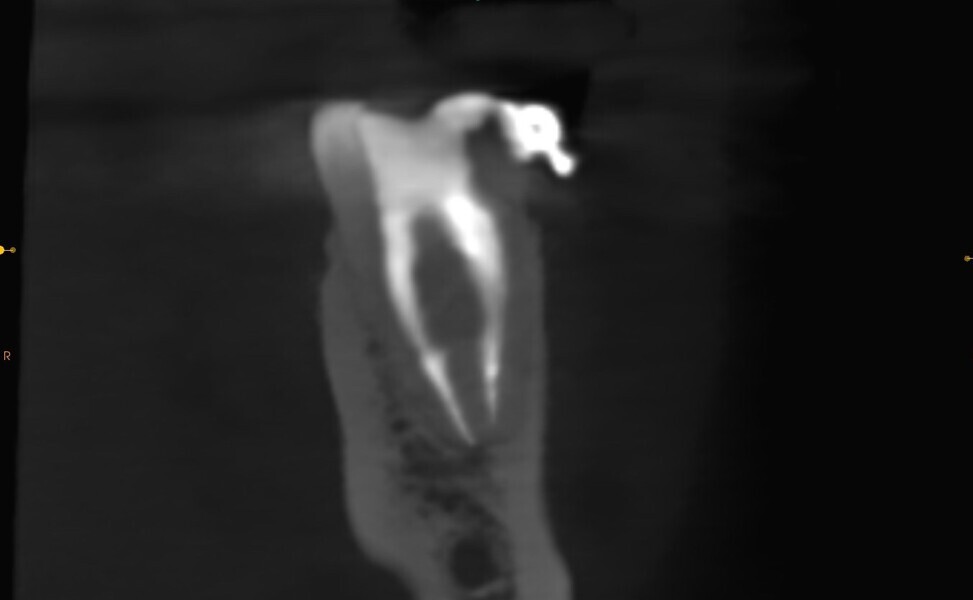

Fig. 2: Pre-op CBCT scan. Broken file far beyond the canal curvature.

Fig. 3: Pre-op CBCT scan. Tip of the broken file located below the junction of the mesiobuccal and mesiolingual canals.

The periapical radiograph and the CBCT scan revealed that the file had broken far beyond the curvature in the mesiobuccal canal and below the junction with the mesiolingual canal. Also, a periapical lesion was visible around the apices of the mesial and distal roots (Figs. 1–3). The length of the file was approximately 5 mm. Bypassing the file through the mesiolingual canal would have been a risky procedure because it may have caused the fracture of the second instrument and the obturation may also have been very challenging. Thanks to SWEEPS technology and a bioceramic sealer, an alternative approach could be taken. After administering anaesthesia and placing a dental dam, the temporary restoration was removed (Figs. 4 & 5). The pulp chamber was rinsed with 5.25% sodium hypochlorite and the irrigant activated with ultrasonics. After cleaning the chamber of the tooth, the dental dam and clamp were rinsed with water and dried and flowable dental dam was placed to seal the tooth and enlarge the space in the pulp chamber for the laser-activated irrigation (Fig. 6). Activation was performed with the SkyPulse laser (Fotona). The AutoSWEEPS mode was chosen. The power of activation was set to 1 W. The flat SWEEPS 300/20 fibre tip was used (Fig. 7). The tip was placed slightly below the orifice of the mesiobuccal canal for the majority of the irrigation with sodium hypochlorite. After 120 seconds of activation with sodium hypochlorite, the tip was placed in the pulp chamber to activate the sodium hypochlorite in all the canals simultaneously for 30 seconds. This procedure was continued for 30 minutes. Only the distal canal was shaped with rotary files, up to size 40/.04. Both mesial canals remained the same size as they were before the file broke during the primary treatment. Finally, the canals were flushed with EDTA activated with AutoSWEEPS at a power of 0.4 W, and sodium hypochlorite was activated for three cycles with AutoSWEEPS at a power of 0.6 W and with a 30-second break for the resting phase. The irrigant flow between the mesiobuccal and mesiolingual canals was rapid, indicating that obturation could be performed.